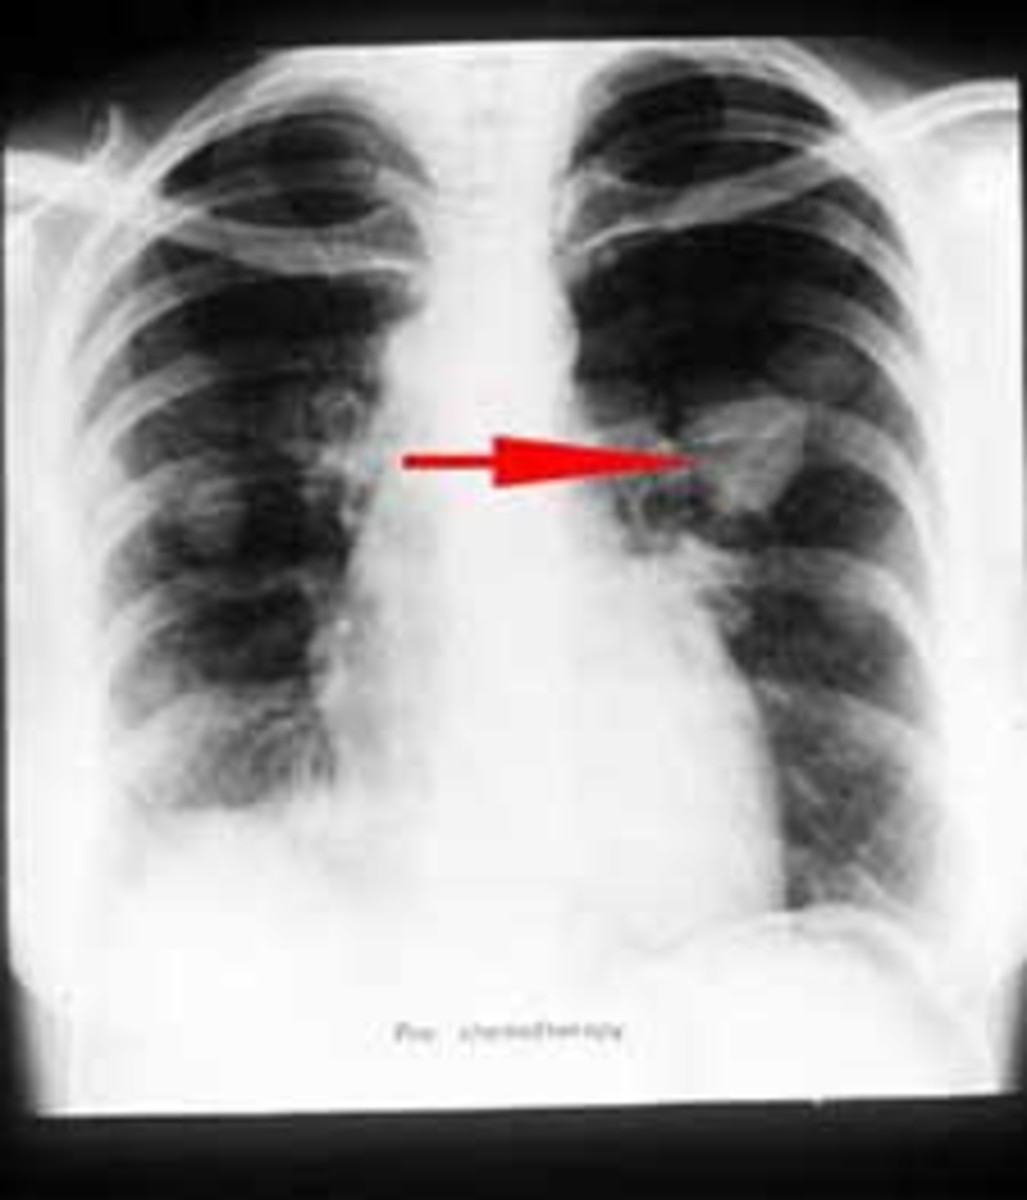

Xray Image of Patient Lungs To Lung Tumor, Lung Cancer or Pneumonia Lung Tumor Cause Pneumonia Studies show that 3 percent of people with lung cancer experience venous. Pneumonia is a pulmonary infection that causes inflammation in the alveoli (small air sacs inside the lungs). Various viruses, bacteria, and fungi can cause pneumonia. Bacteria, viruses, and fungi cause. Dyspnea (shortness of breath) swelling of the arms, chest, face, and neck. It is one of the leading. Lung Tumor Cause Pneumonia.

Lung Cancer or Pneumonia. Doctor check up xray image have problem lung Lung Tumor Cause Pneumonia Pneumonia is a pulmonary infection that causes inflammation in the alveoli (small air sacs inside the lungs). Between 50 percent and 70 percent of people with lung. Various viruses, bacteria, and fungi can cause pneumonia. Pneumonia and lung cancer are often experienced at the same time. Dyspnea (shortness of breath) swelling of the arms, chest, face, and neck. Abnormal cells. Lung Tumor Cause Pneumonia.